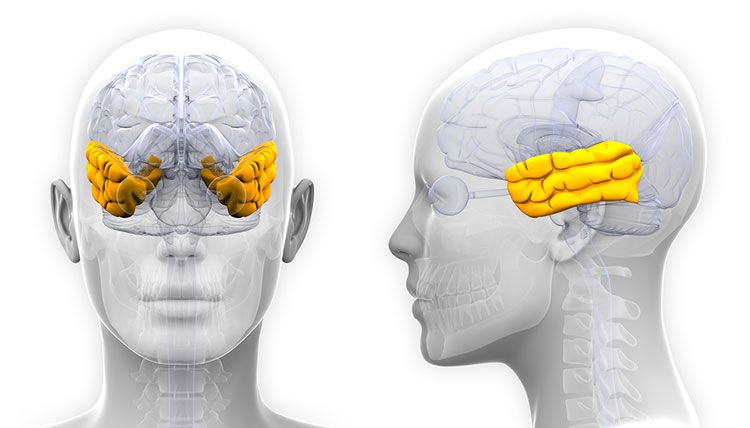

Ubicación

El área de Broca ubicada en la tercera circunvolución frontal (en el lóbulo frontal) del hemisferio cerebral izquierdo, si bien en algunos casos excepcionales se encuentra en el hemisferio derecho. Concretamente, según el mapa de Brodmann, ocupa las áreas 44 y 45 de Brodmann, cerca del ojo y pegado a la parte frontal del lóbulo temporal.